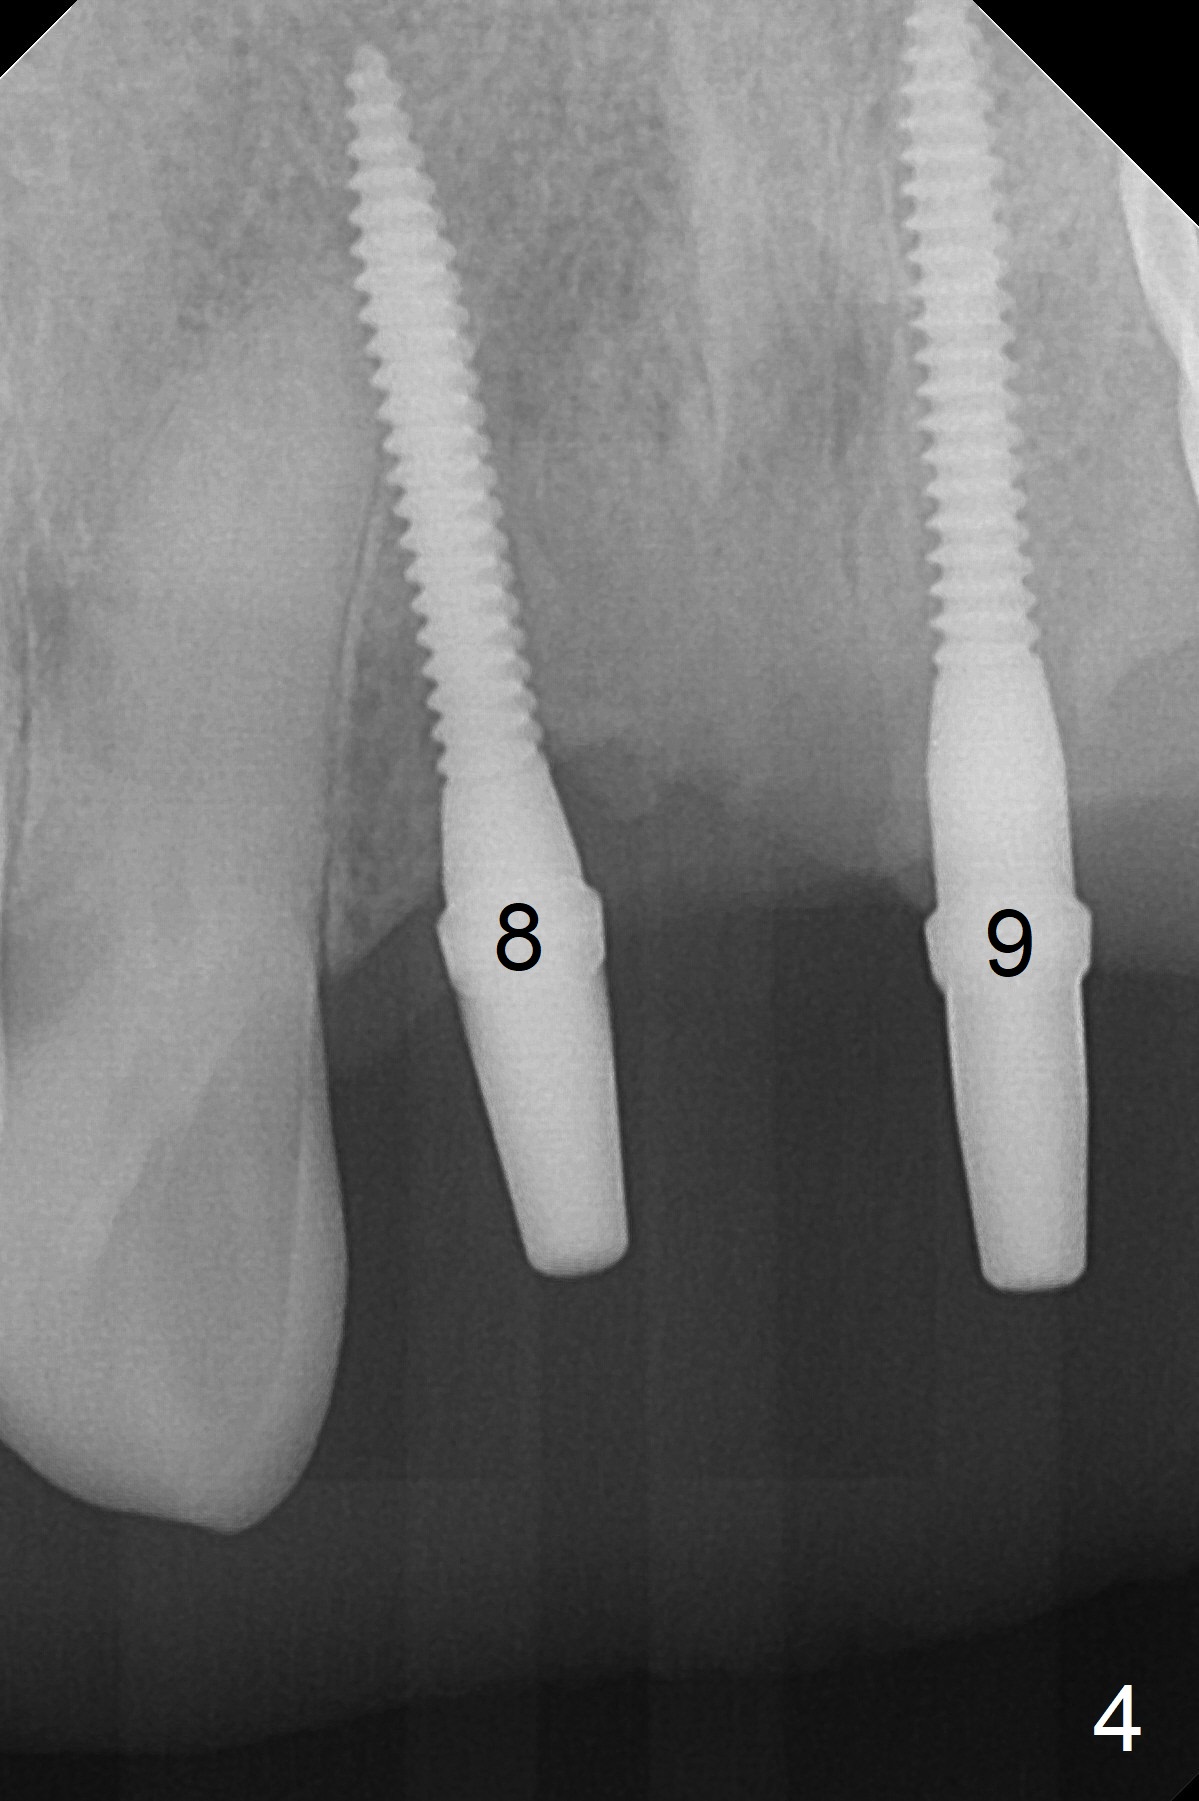

For implant placement of the atrophic ridge (Fig.1), osteotomy starts at #8 and 9 (Fig.2). Change in trajectory at #8 seems acceptable (Fig.3 (arrowheads: upper midline suture)). But it relapses when a 2x14(2) mm implant is placed (Fig.4 (2x14(4) mm at #9)). It appears that a drastic change in trajectory is necessary (Fig.5). In fact it is difficult to change the trajectory with the flexible 1.2 mm drill. Lindamann bur can be used for this purpose initially (coronally). The osteotomy should be moved mesially prior to reuse of the 1.2 mm drill for depth.